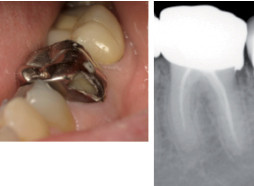

La situation clinique ci-contre permet de bien illustrer l’ensemble de ces règles qui, globalement, sont celles appliquées en NGAP. Avec une différence notable, celle du codage de tous les actes (remboursables ou non) par la CCAM. Ce qui permet de légitimer, aux yeux du patient, les actes non pris

en charge et de réconforter leur « indication médicale ».

La couronne coulée est infiltrée et doit être déposée.

Il est envisagé de reprendre les soins endodontiques et réaliser par la suite une couronne céramo-céramique.

Le traitement envisagé comprend donc, de manière séquentielle, les actes suivants :